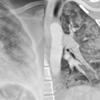

contusion/laceration, pneumo